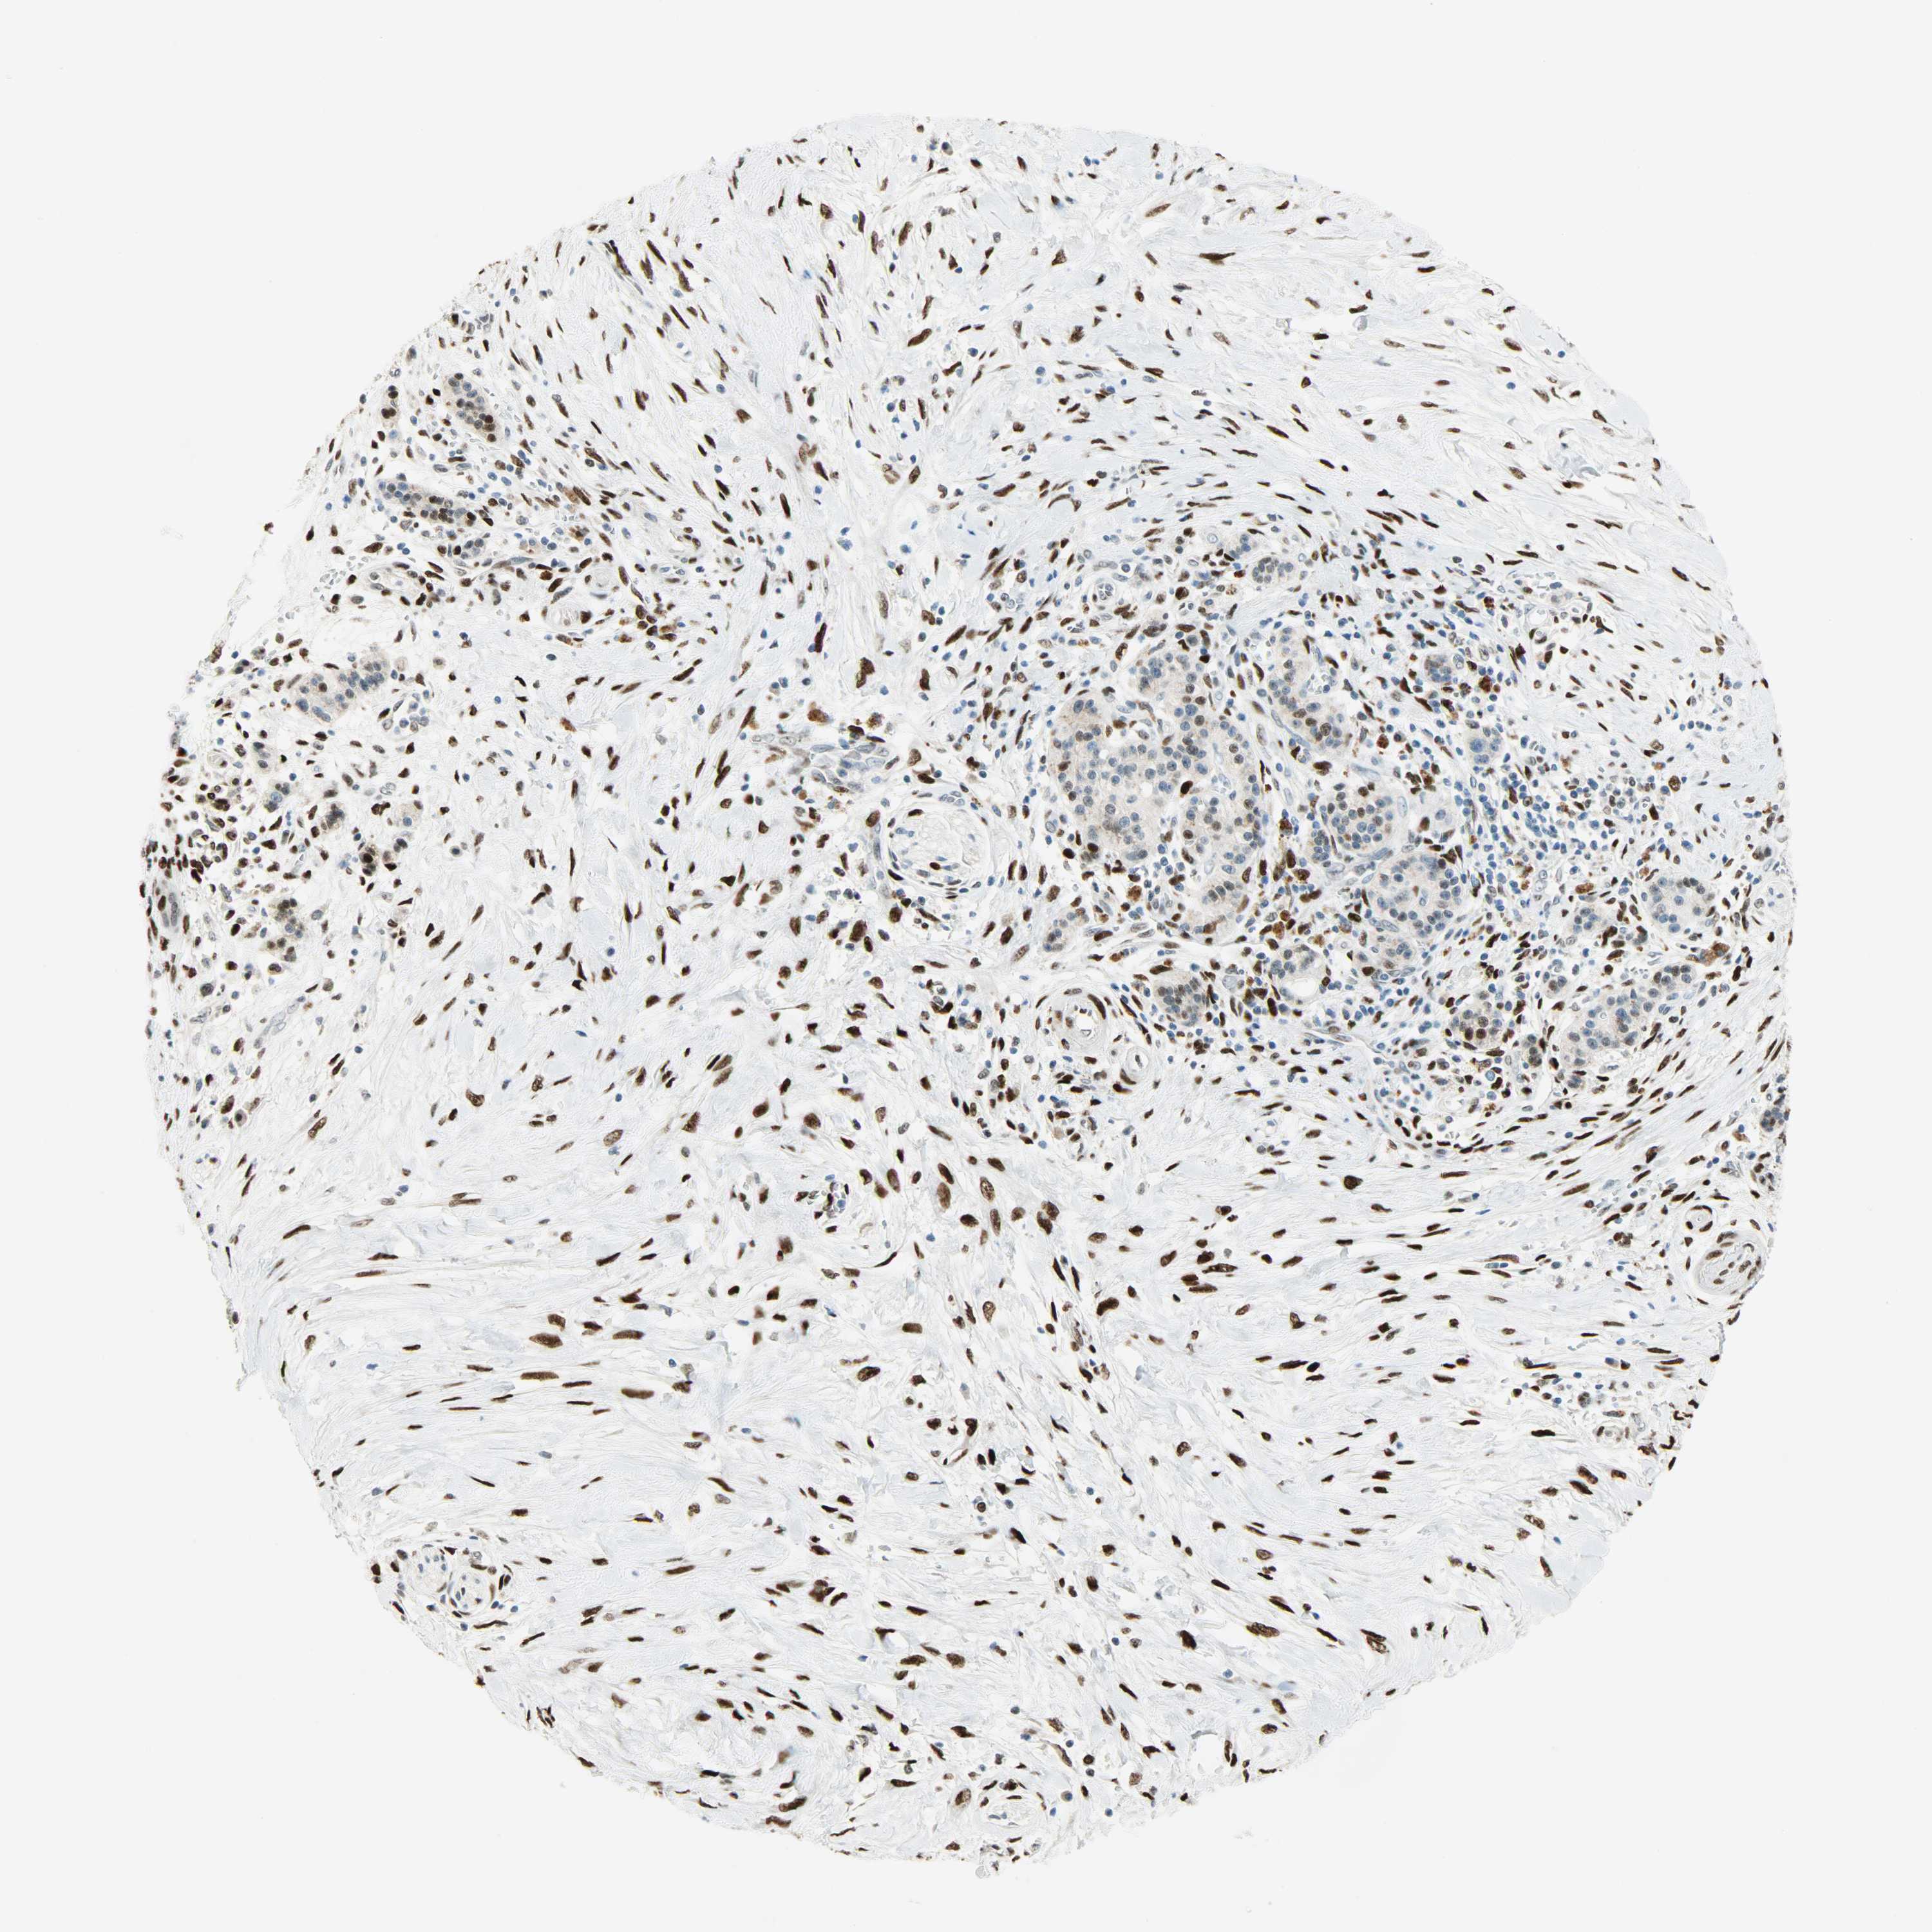

PANCREATIC CANCER - Protein expressioni

A mouse-over function shows sample information and annotation data. Click on an image to view it in a full screen mode. Samples can be filtered based on level of antibody staining by selecting one or several of the following categories: high, medium, low and not detected. The assay and annotation is described here.

Note that samples used for immunohistochemistry by the Human Protein Atlas do not correspond to samples in the TCGA dataset.

Antibody stainingi

Antibody staining in the annotated cell types in the current human tissue is reported as not detected, low, medium, or high, based on conventional immunohistochemistry profiling in selected tissues. This score is based on the combination of the staining intensity and fraction of stained cells.

Each image is clickable and will lead to virtual microscopy that enables deeper exploration of all samples and also displays staining intensity scores, fraction scores and subcellular localization as well as patient and tissue information for each sample.

Antibody HPA019149

Antibody CAB004464

Staining

High

Medium

Low

Not detected

Intensity

Strong

Moderate

Weak

Negative

Quantity

>75%

75%-25%

<25%

None

Location

Nuclear

Cytoplasmic/membranous

Cytoplasmic/membranous,nuclear

Adenocarcinoma, NOS

Adenocarcinoma, metastatic, NOS